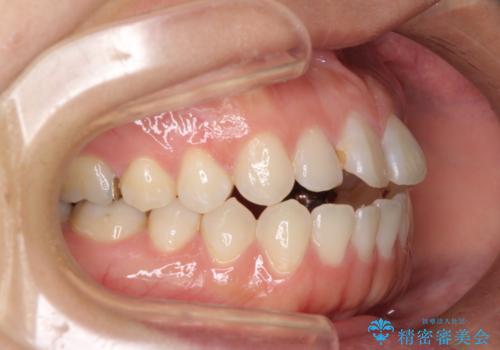

開咬と変色した前歯 インビザライン矯正とオールセラミッククラウン治療

- 前歯の開咬と失活により変色した前歯を気にして来院された患者様です。

開咬の治療は、前歯を閉じるように引っ張り出すよりも、上下臼歯を圧下(骨内にめり込ませる)させることで進める方が長期的に安定した歯列を維持できます。

インビザラインは臼歯の圧下を効果的に行えるため、インビザラインを用いて矯正治療を行うこととしました。

矯正治療が概ね終了した時点で前歯をオールセラミッククラウンにて補綴治療を行い、その後インビザラインにて細かい部分を仕上げていくことしました。